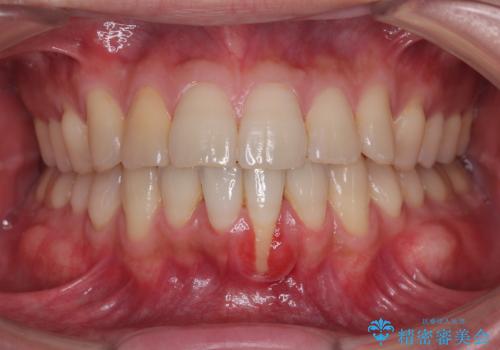

- 他院で矯正治療を終えた結果、下顎前歯の歯肉が退縮してしまい、歯根が見えていることが気になるとのことで来院された患者様です。

歯肉退縮に対して、上顎からの結合組織移植術(CTG)により、歯根の被覆を行うとともに、歯肉の厚みを増すことで将来の退縮リスクを抑制することとしました。